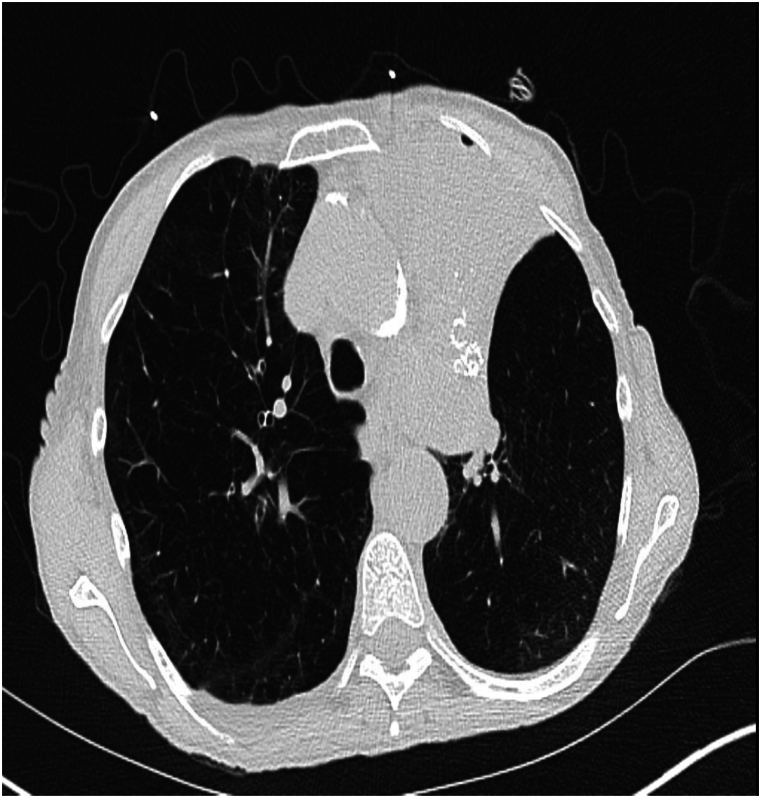

Chronic obstructive lung disease is the third leading cause of death worldwide. It affects the airways and lung parenchyma leading to emphysema. Bronchoscopic lung volume reduction is another strategy that aims to reduce air trapping and hyperinflation, leading to improvement in symptoms and pulmonary function. Several techniques have been employed, one of them is the blocking method using Zephyr or Spiration valves. The use of both valves is approved by the Food and Drug Administration view their established efficacy in improving lung functions, quality of life and survival. Although they have a relatively safe profile, several adverse events have been reported, pneumothorax being the most common and pleural effusion being the least reported. We show herein, a case of 74-year-old female presenting with pleural effusion secondary to bronchoscopic lung volume reduction. Although uncommon, highlighting this potential outcome is crucial.